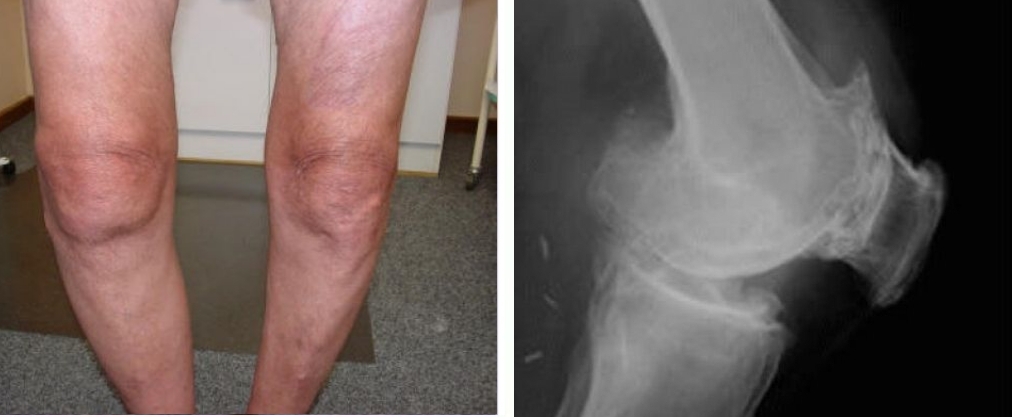

Kerusakan sendi lutut, kelengkungan parah pada lutut, serta nyeri tajam yang terus-menerus, terutama saat melakukan gerakan sekecil apa pun.

Lihat foto-foto ini. Inilah yang terjadi pada mereka yang tidak memperhatikan gejala. Hari ini, mereka adalah orang-orang yang tak berdaya, dan banyak di antara mereka tidak memiliki siapa pun untuk membantu. Apakah Anda menginginkan nasib seperti itu?